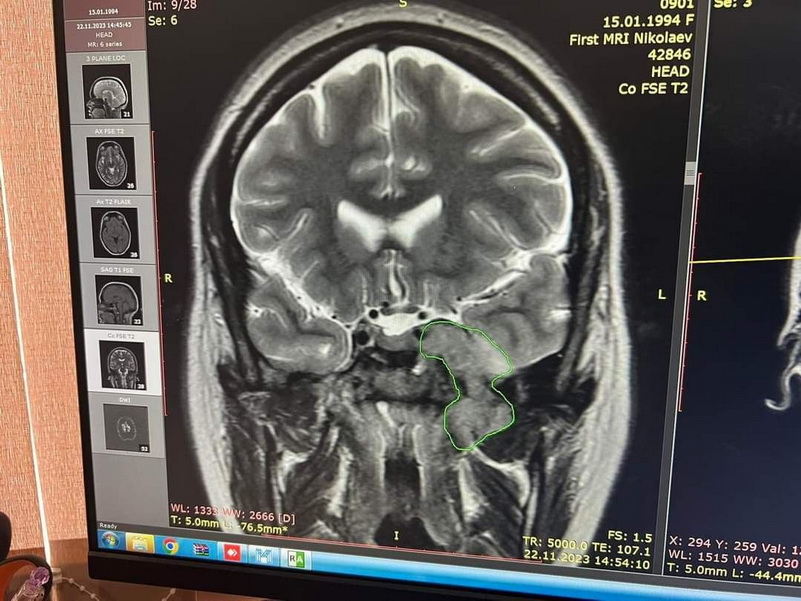

«На фото — красивая и улыбающаяся Татьяна, которая заболела очень тяжелой болезнью (опухоль головного мозга), на ее лечение нужно очень много средств. Операция нужна уже, но, к большому сожалению, всей суммы нет.

В киевском институте нужна операция, будет стоить около 5 тысяч долларов, а у нас сейчас есть только половина этой суммы», — говорит свекровь Татьяны и умоляет всех неравнодушных о помощи.